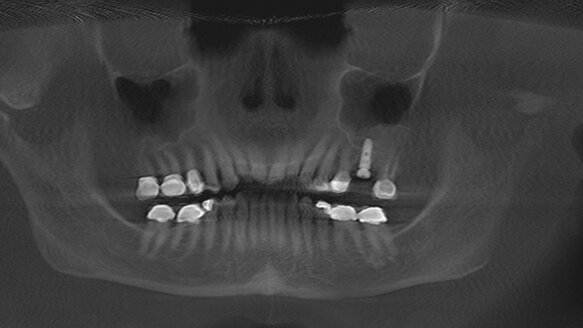

A sinus lift is a surgery that adds bone to the maxilla in the area of the molars and premolars. It’s sometimes called a sinus augmentation. The bone is added between the floor of the maxillary sinus and the Schneiderian membrane. To make room for the bone, the sinus membrane has to be moved upward, or “lifted.” Any dentist who is trained to do it can do a sinus lift. Tatum, the originator of the procedure, is a general dentist.

The sinus lift techniques have undergone numerous modifications through the years. In 1975, Tatum was the first to perform the lateral window technique in conjunction with autogenous bone grafting for the purpose of placing dental implants in the newly formed bone. Although the lateral window technique is highly invasive, it is a necessary procedure. In 1994, Summers, who was in pursuit of a less invasive sinus lift method, made the surgical protocol easier by offering crestal approach or osteotome technique.

The lateral window technique is being used more sparingly these days. There are several methods available that have allowed us to effectively raise the Schneiderian membrane 5–7 mms or more routinely and place the implant simultaneously, as long as we have enough crestal bone to get primary stability. This technique is safer for the patient, and it reduces the chance that an infection will occur.

Lastly, with the evolution of safer and more predictable sinus lift methods, more dentists are able to successfully perform the procedure, which allow more patients to have implants in the posterior maxilla.